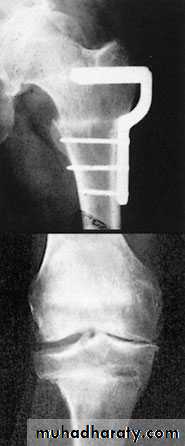

3- realignment osteotomy

3- realignment osteotomy like proximal tibial osteotomy: Osteoarthritis usually affects the inside half (medial compartment) of the knee . This can lead to the lower extremity becoming slightly bowlegged or a genu varum deformity.Osteotomy decrease venous congestion, removed fibrosed sensory end , increased blood supply ,due to fracture induction, and re-aligning the angles (this places more of the weight-bearing force into a healthier compartment ).

A wedge of bone is removed or added to the upper tibia. A staple or plate and screws are used to hold the bone in place until it heals

1- Arthroplasty: replacement of joint by prosthesis can be performed and give excellent results especially in hip and knee, other joints also can be replaced. ( articular surface of both side of joint resected and replaced by artificial joint). It provide painless mobile joint.2- Arthrodesis if stiffness not interfere with function like ankle and foots joints , (articular surface of both side of joint resected and the two bone fused to each other in physiological position). ). It provide painless stiff limb.